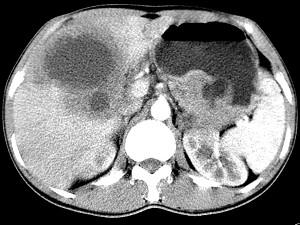

问题 女,61岁,上腹部疼痛一个月,食欲减退,消瘦,CT所见如图,最可能的诊断是 ( )

选项 A、肝包虫病 B、原发性肝癌 C、肝转移瘤 D、胃癌肝转移 E、肝脓肿

答案 D